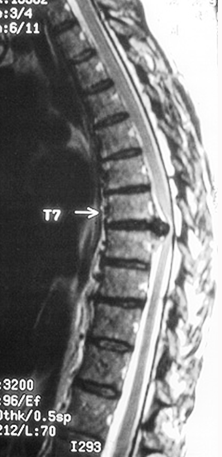

Endoscopic surgery has special applications for treatment of spinal problems particularly in the thoracic spinal column. Where endoscopic procedures for cervical and lumbar disorders have limited and less predictable outcomes, thoracic disc and spinal problems are often treated most successfully with minimally invasive “thoracoscopic or VATS (video-assisted endoscopic thoracic surgery).”

Dr Johnson has been one the pioneers in developing endoscopic spinal surgery and in particular thoracic spinal procedures and has published widely and lectured on the treatment of disc herniation, spinal cord compression in the thoracic spine.